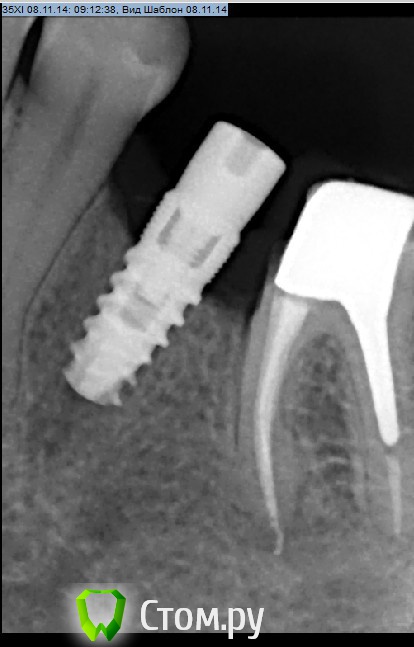

Рустам Опубликовано 11 ноября, 2014 Поделиться Опубликовано 11 ноября, 2014 Интегрированный имплантат MIS. Как бы поступили в данной ситуации коллеги. В полости рта имплантат на уровне десны, вестибулярно выше десны на 0.5 мм.Отправил переустановить. 1 Ссылка на комментарий

Рустам Опубликовано 11 ноября, 2014 Автор Поделиться Опубликовано 11 ноября, 2014 Хирург контрольный снимок не делал что ли.. судя по снимку видно, что ложе под имплантат не полностью заполнено. Мне интересно, как пациенту преподнесли необходимость повтороной имплантации?А если бы пациент пришел уже с интегрированным имплантатом через 3 месяца..представляю себе реакцию такого пациента ))))Хирург делал снимок после постановки имплантата,имплантат был поставлен выше кости на 2 мм, внятного объяснения почему не вровень с костью не получил, хотя условия хорошие.Вообще пациент пришел ко мне спустя 3 месяца с уже интегрированым имплантатом)))Сказал хирургу чтобы сама объяснила пациенту о необходимости переустановки имплантата. Ссылка на комментарий